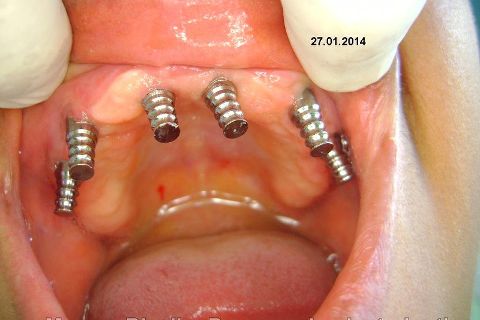

Atualização do caso clínico que já postei, "REABILITAÇÃO EM MAXILA ATRÓFICA COM IMPLANTES", um caso que inclui expansão do rebordo estreito com cinzel e martelo, expansores rosqueáveis, enxerto e instalação dos implantes distais inclinados tangenciando seio maxilar. Inclui esvaziamento do forame nasopalatino e preenchimento com biomaterial para instalação de dois implantes próximos dele. Cirurgia realizada em única sessão, com instalação dos 6 implantes. Para os colegas que não conheceram e/ou esqueceram da apresentação, este é o resumo do caso na fase cirúrgica.http://www.youtube.com/watch?v=BtvexFexRPA&hd=1

FASE PROTÉTICA DA REABILITAÇÃO EM MAXILA ATRÓFICA...incluindo a reabertura, instalação dos minipilares e PTR provisória reembasada sobre os cilindros de proteção.